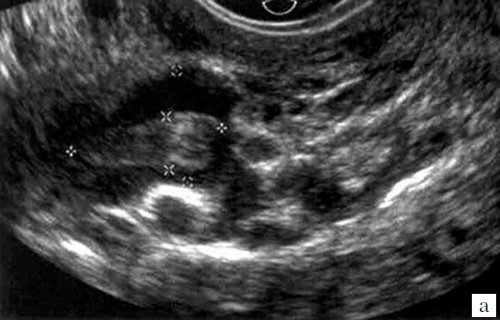

При ТВУЗИ тромб визуализировался как аваскулярное образование, частично или полностью перекрывающее просвет венозного сосуда. Эхогенность тромба, в зависимости от давности его возникновения, колебалась от низкой или средней (рис. 1, 2) до высокой, вплоть до наличия кальцинированных включений (рис. 3, 4).

а) В режиме серой шкалы анэхогенный тромб размером 2,2x1,1 см практически не визуализируется.

б) В режиме ЦДК окрашивания просвета вены не отмечается.